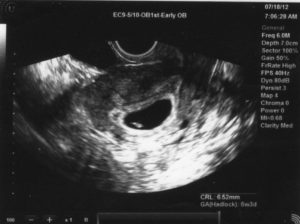

Обследование в этот период проводится при помощи вагинального датчика. Врач наносит на него специальный гель, который позволяет осуществить контакт и увидеть изображение внутренних органов женщины.В этот период доктор отмечает состояние эндометрия. Также проводится измерение детородного органа в трех плоскостях. Помимо этого врач обследует придатки. В нормальном состоянии к этому сроку в одном из яичников должно находиться желтое тело, которое образовалось после овуляции.

Если уже видно плодное яйцо, то производится его замер. Также врач осматривает его полость и отмечает наличие или отсутствие желточного мешочка, который впоследствии станет зародышем и эмбрионом.

В некоторых случаях на УЗИ диагностируется замершая беременность (3-4 недели). Такой вердикт может вынести неопытный специалист. Стоит отметить, что на этом сроке еще нельзя обнаружить эмбрион и уж тем более увидеть его сердцебиение.

Единственное, что может стать результатом данного обследования, — это выявление плодного яйца. Диагноз «неразвивающаяся беременность» может быть поставлен ошибочно из-за отсутствия эмбриона. Не стоит сразу бежать на выскабливание.

Подождите еще две недели, и, возможно, к этому сроку уже появится эмбрион в плодном яйце.